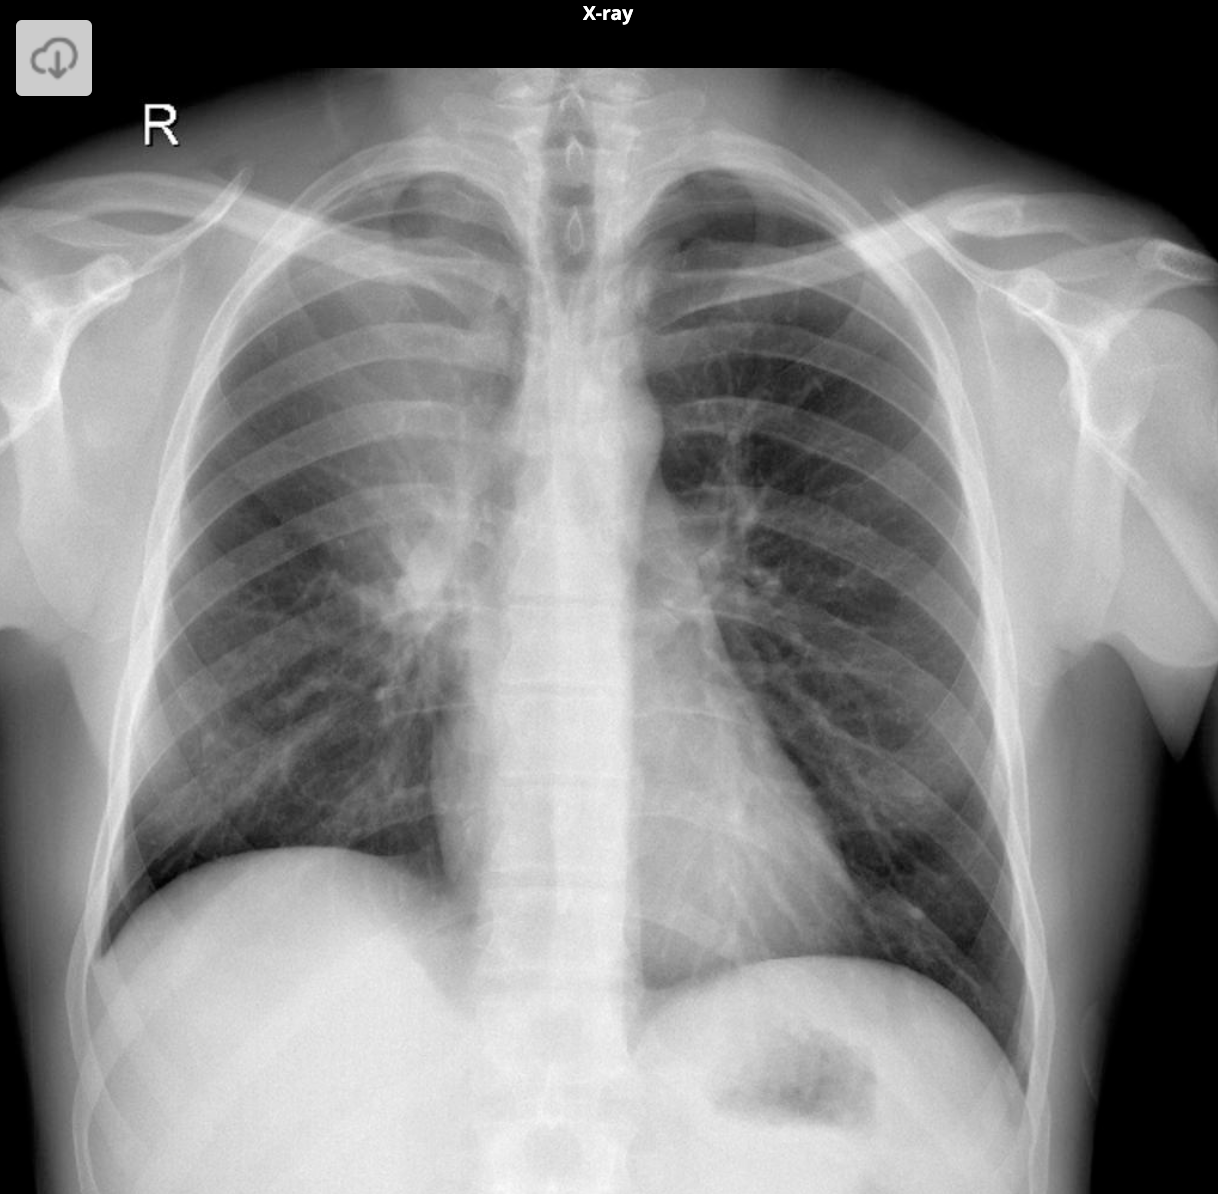

What are the features of of LUL collapse on CXR

Luftsichel sign = due to hyperlinflation of the superior segment of LLL interposing itself between the mediastinum and collapsed LUL

L hilum drawn upwards

Almost horizontal course if LMB and vertical course of LLL bronchus

Elevation of L hemidiaphragm

Peaked/ tented hemidiapgram

Crowding of L ribs

Shift of mediastinum to L

Hazy opacification of the L hemithorax

What are the features of LUL collapse on CT scan

Triangular opacification in axial images, thinner at hilum

Anterior oblique fissre rotates anteromedially